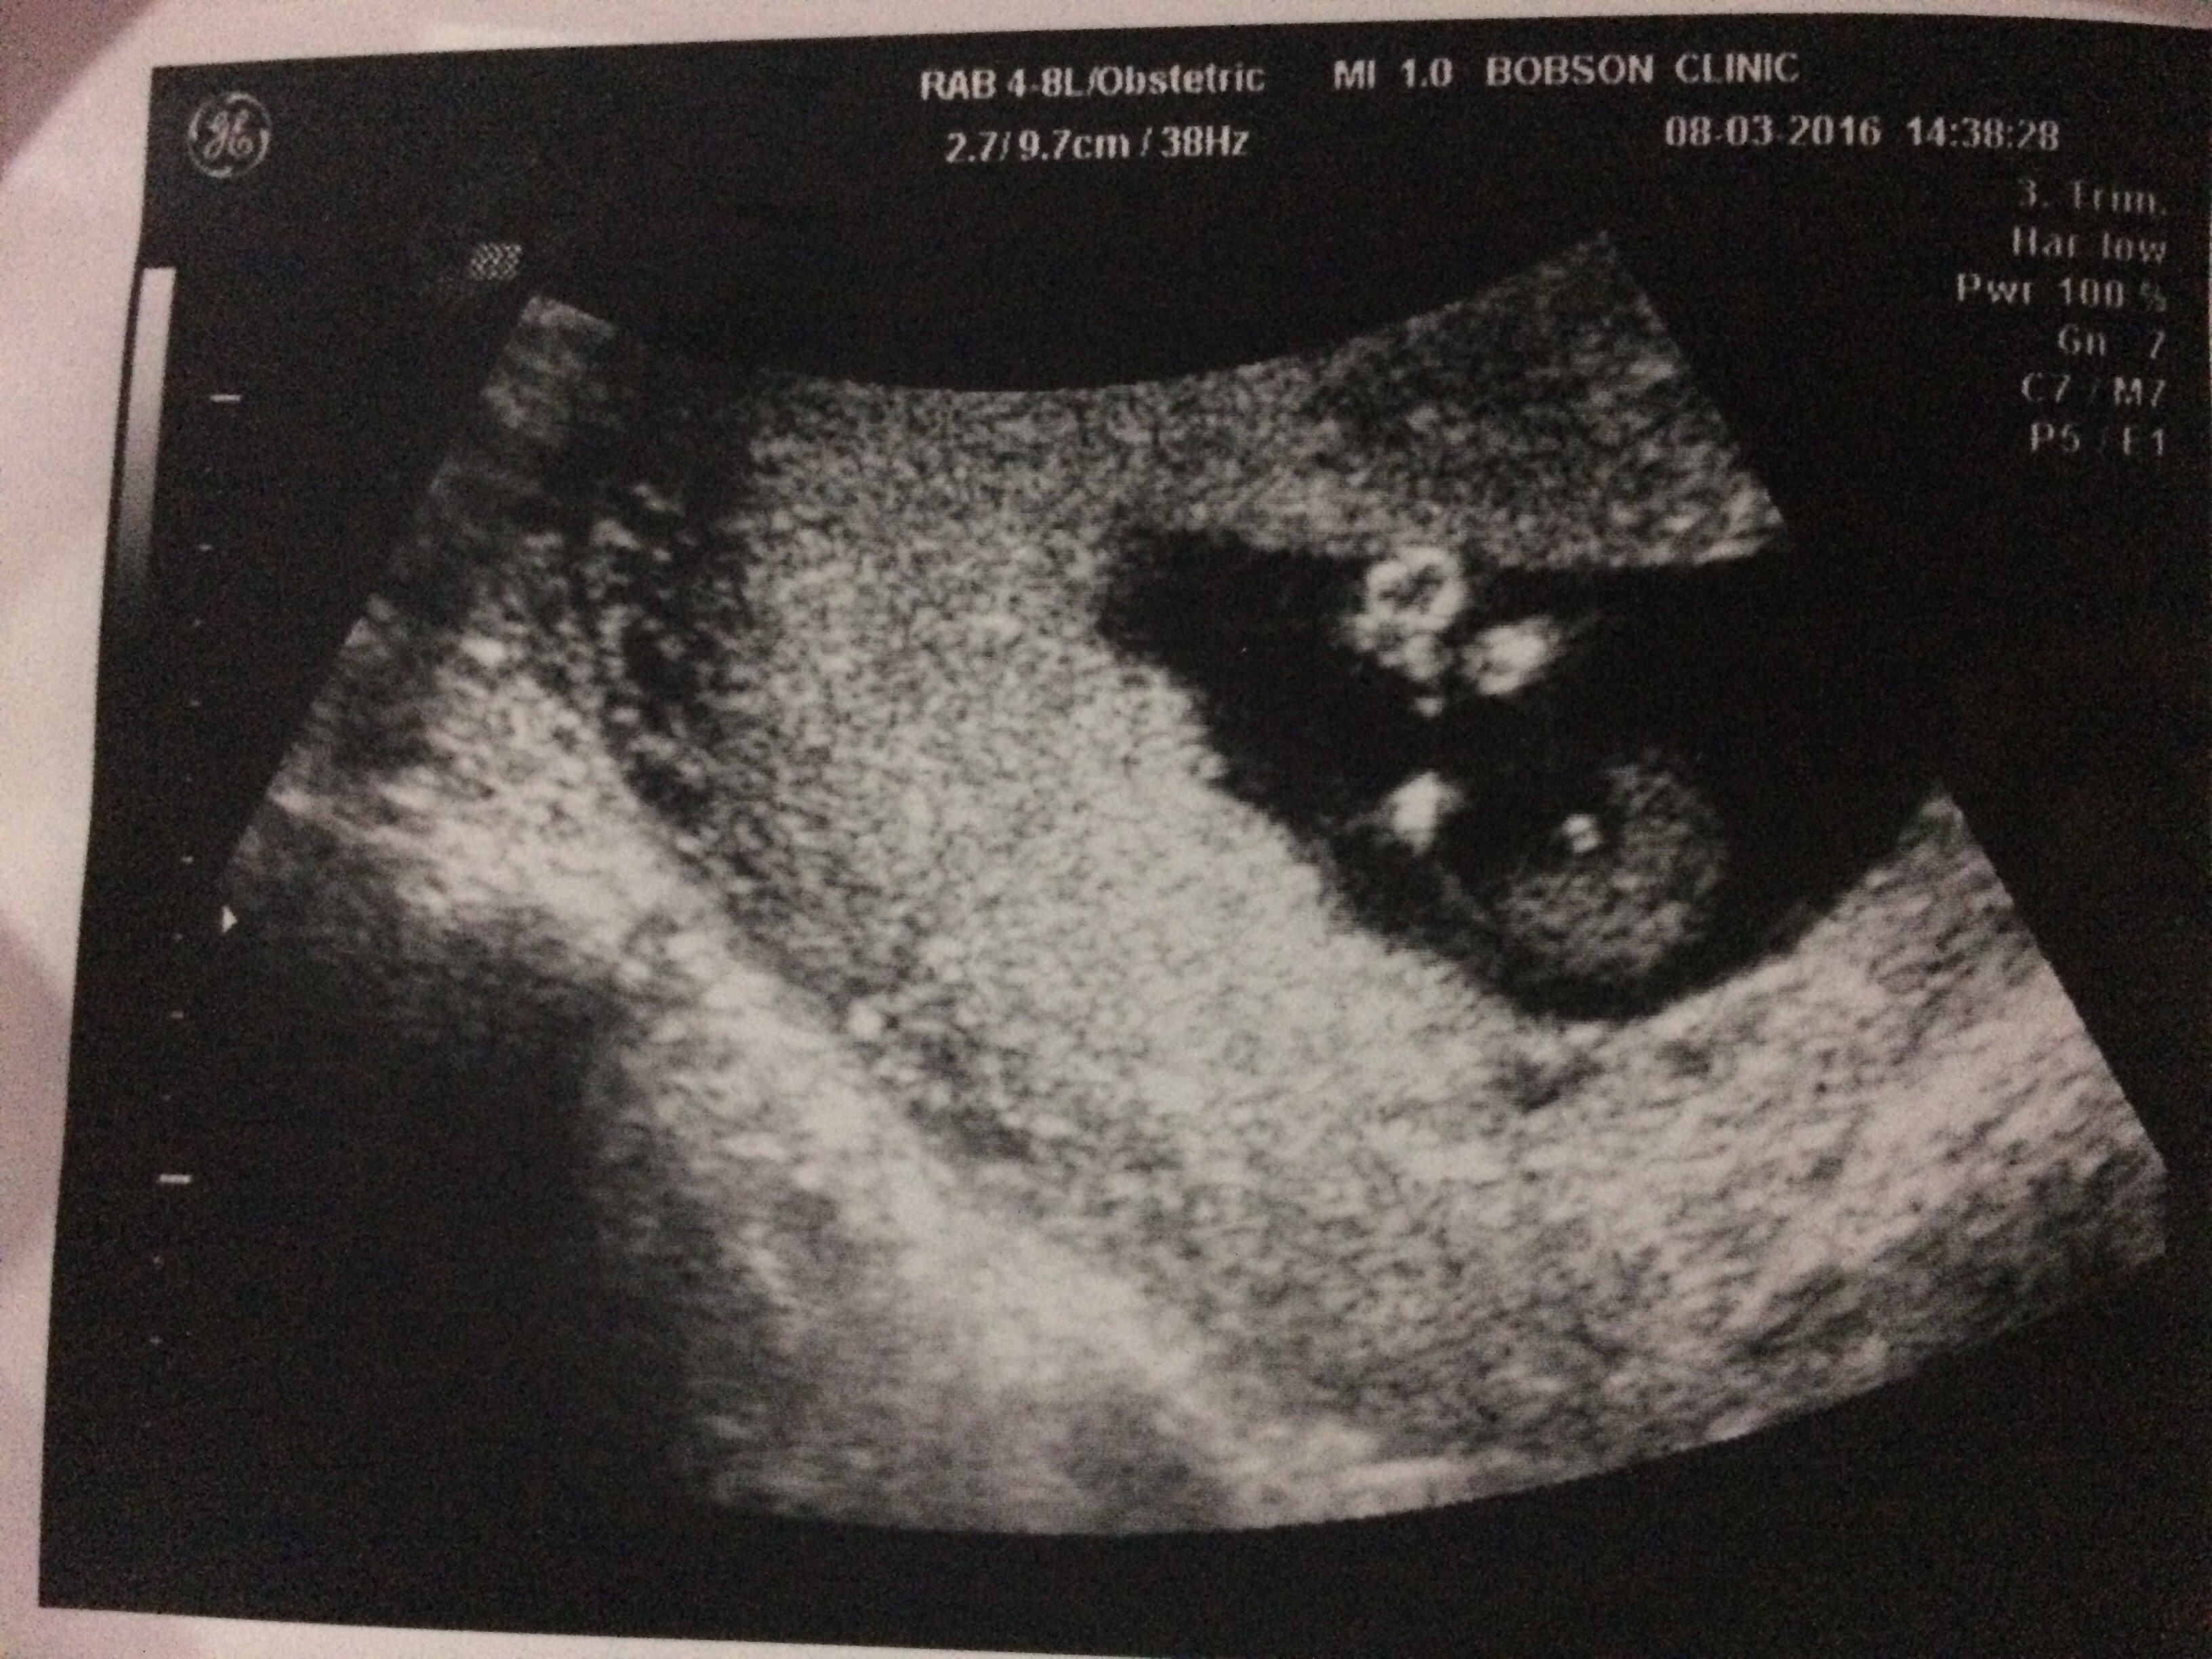

附上12週雞雞照給大家看!

大家覺得是雞雞還是臍帶呢?